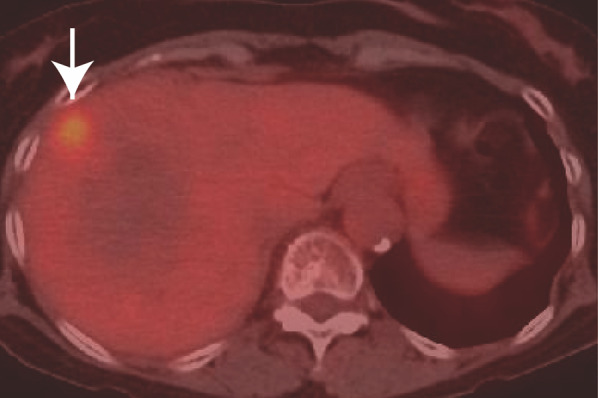

The patient underwent 4 years and 6 months of follow-up surveillance according to the Japanese Society for Cancer of the Colon and Rectum (JSCCR) Guideline for the treatment of colorectal cancer. Serum tumor markers, which are recommended to be examined every 6 months after 3 years, remained within the normal ranges until 4 years and 6 months after ileocecal resection. She had been diagnosed with liver cysts but not liver tumors on an enhanced computed tomography (CT) scan until 5 years after ileocecal resection. However, due to the patient’s fatigue, serum examinations were canceled at 5 years. After persuading her to undergo the final follow-up examination three months later, the serum carbohydrate antigen 19-9 (CA19-9) level increased to 929 U/ml, not observed 9 months earlier (4.5 years after ileocecal resection), with no detectable mass lesions on abdominal ultrasound sonography (AUS). Other parameter levels were within normal ranges in the serum analysis. We suggested that the patient undergo an enhanced CT scan. However, she hesitated to accept our recommendation, expressing disappointment with the results, and declined further examinations and treatment. Two weeks later, she presented herself, and subsequent dynamic enhanced CT detected an ambiguous low-density tumor measuring 2.2 × 2 cm in liver segment 8 (Fig. 1a), and serum CA19-9 levels further increased to 2023 U/ml. The tumor exhibited delayed enhancement in the inner part and marginal enhancement in all phases (Fig. 1b–d). Peripheral intrahepatic bile duct dilatation and regional lymph node swelling were absent. Magnetic resonance imaging (MRI) revealed low intensity on T1-weighted images (Fig. 2a), high intensity on T2-weighted images (Fig. 2b), and high intensity on diffusion-weighted images (DWI) (Fig. 2c). Gadolinium-ethoxybenzyl-diethylenetriaminepentaacetic acid (Gd-EOB-DTPA) MRI showed marginal enhancement in the arterial-to-venous phase (Fig. 2d and e) and hypointensity in the hepatocellular phase (Fig. 2f). Fluorodeoxyglucose-positron emission tomography (FDG-PET) revealed high integration into the tumor (SUVmax, 5.9; Fig. 3) without any suspected metastasis or lymph node metastasis 10 days after tumor detection on CT. Tests for hepatitis B surface antigen and hepatitis C virus antibodies were negative. Further gastrointestinal workup, including upper and lower endoscopies, yielded negative results.

Fig. 3.

FDG-positron emission tomography (PET). PET shows high integration (SUVmax:5.9) in the tumor